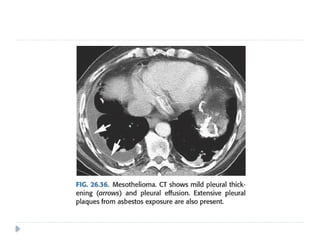

MALIGNANT MESOTHELIOMA

⚫ Highly malignant and locally aggressive tumor

⚫ 6th or 7th decade of life

⚫ Associated with asbestos exposure, with an average latency of

On imaging :

⚫ Diffuse nodular pleural thickening – pleura along the

intercostal spaces, costophrenic angles and lung apices

are involved.

⚫ Pleural plaques (latent period of formation is 20yrs; strong

indicator of asbestos exposure): usually seen adjacent to ribs.

Involving sixth to ninth rib. These themselves are not

premalignant

⚫ Pleural effusion

⚫ Calcifications may be seen along diaphragmatic pleura.